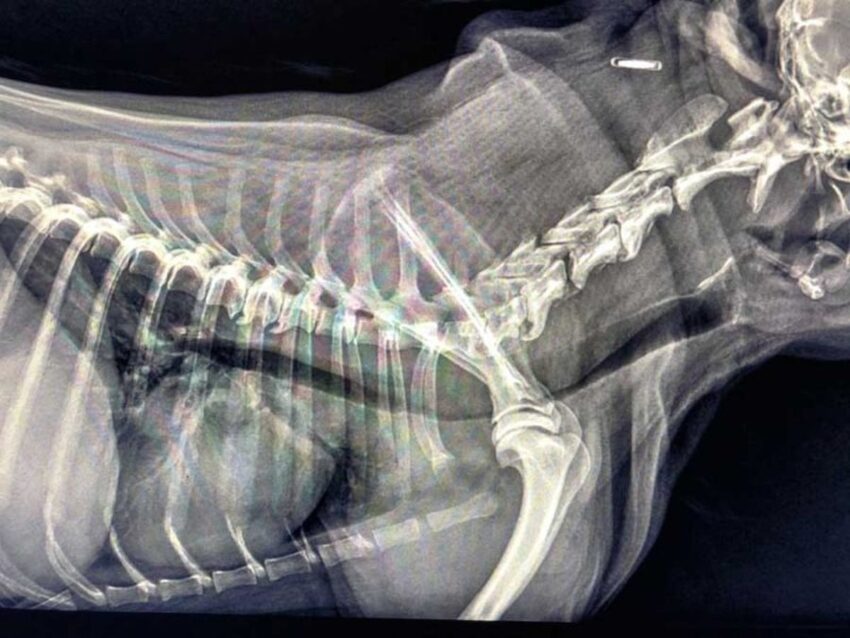

Zapadanie tchawicy u psów (TCS-Tracheal Collapse Syndrome)

Źródło: https://wetgliwice.pl/ Zapadanie tchawicy u psów (TCS-Tracheal Collapse Syndrome) Zapadanie tchawicy u psów (TCS-Tracheal Collapse Syndrome) jest przewlekłą chorobą układu oddechowego obserwowaną głównie u raz małych i miniaturowych (Yorkshire terrier, Szpic miniaturowy, Chihuahua). Choroba ta polega na „zapaści” tchawicy co w znacznym stopniu ogranicza jej drożność. Odnotowuje się dwa procesy przyczyniające się do rozwoju tej choroby….